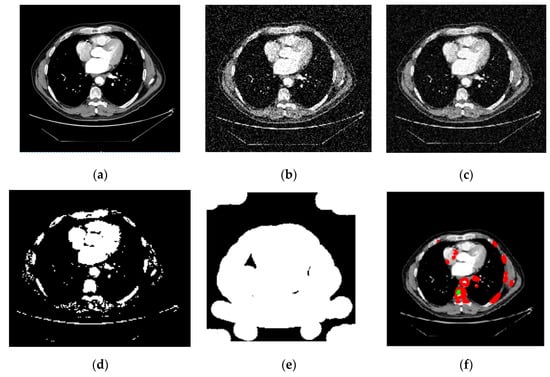

The CT image of lung cancer used as the input, as shown in Figure 9a, is taken from the LIDC-IDRI dataset. The median filter was applied to the input picture as a first step to eliminate any artifacts that may have been produced during the image-capturing process for experimenting. It was necessary to divide the Region of Interest (ROI) into many parts in order to determine the specific area or region of interest that was wanted. In order to obtain the ROI, we first had to transform the grayscale picture into a binary form. Then, we used a morphological operation in the form of dilation, which gave us a decent but distorted image full of holes. After applying the watershed transformation or image dilation, we obtained a segmented image. This allowed us to fill in the gaps. Finally, we went back over the photos and traced the edges of the nodules.

Figure 9.

CT Image classification procedure. (a) Original Image. (b) Noisy Image. (c) Adaptive Filtering PSNR. (d) Dilate image. (e) Watershed Transform. (f) Lung cancer type: malignant.

We employed classification strategies in the form of Inception-V3 by using segmented pictures from each of the three classes. Figure 9a–f depicts the results of the Ct image processing with noise addition, noise reduction, dilation, watershed transformation, image segmentation, and the corresponding classification output. We began by establishing certain boundaries when starting CNN’s training process. Epochs were randomly chosen to determine the number of required iterations to achieve a high categorization accuracy. After implementing various training strategies, we achieved an accuracy of 98.96% and 0.0279 mini-batch loss value. Figure 10 depicts the training duration and validation accuracy, whereas Figure 11 depicts the accuracy and validation loss. Both Figures are located on the same page. The segmentation and preprocessing steps were reliably executed. When we first started training, we noticed that the validation accuracy eventually reached 90% once the training approached the fifth epoch.